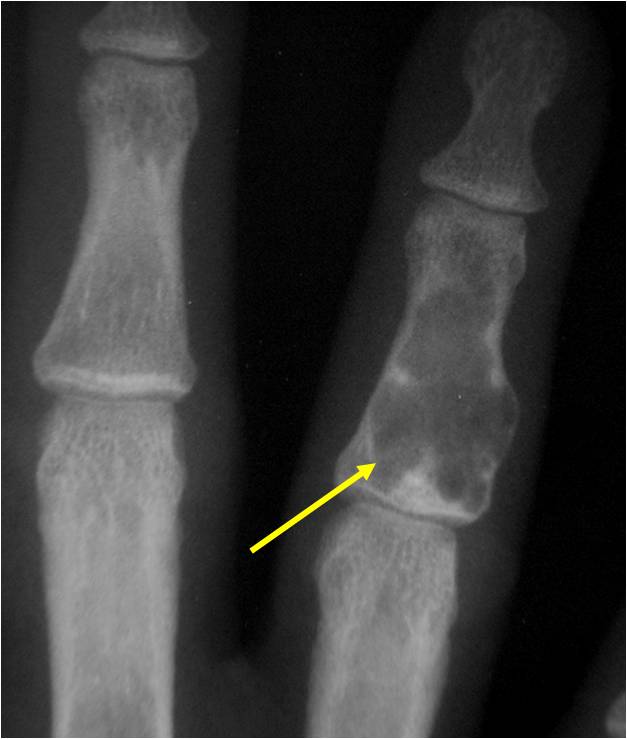

- Phalangeal tumors may be painful due to stress fractures

- Cortex may be scalloped and thinned in the phalanges

- Geographic lytic lesion

- Expansile remodeling with thinned cortex

- Chondroid matrix with calcifications in majority of tumors

- There should never be any cortical destruction nor a soft tissue component. If this exists then the tumor must be a chondrosarcoma.

- Endosteal scalloping and cortical expansion is acceptable for phalangeal tumors. In most benign long bone cartilage tumors there is minimal endosteal scalloping but there should be no cortical expansion nor thickening. There should be no cortical destruction and no soft tissue component associated with an enchondroma. Cortical destruction, periosteal thickening, cortical expansion and a soft tissue component indicates a chondrosarcoma of the long bone.

- Cortical destruction and a soft tissue mass

- Endosteal erosion>2/3 cortical thickness on a CT scan